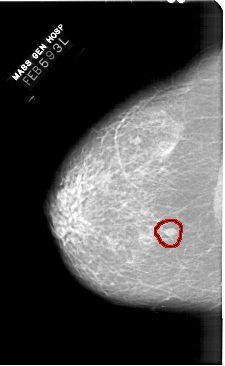

A_1443_1.LEFT_MLO

LEFT_MLO LINES 5791 PIXELS_PER_LINE 3961 BITS_PER_PIXEL 12 RESOLUTION 43.5 OVERLAY

FILE: A_1443_1.LEFT_MLO.OVERLAY

TOTAL_ABNORMALITIES 1

ABNORMALITY 1

LESION_TYPE MASS SHAPE OVAL MARGINS ILL_DEFINED

ASSESSMENT 4

SUBTLETY 3

PATHOLOGY BENIGN

TOTAL_OUTLINES 1

BOUNDARY